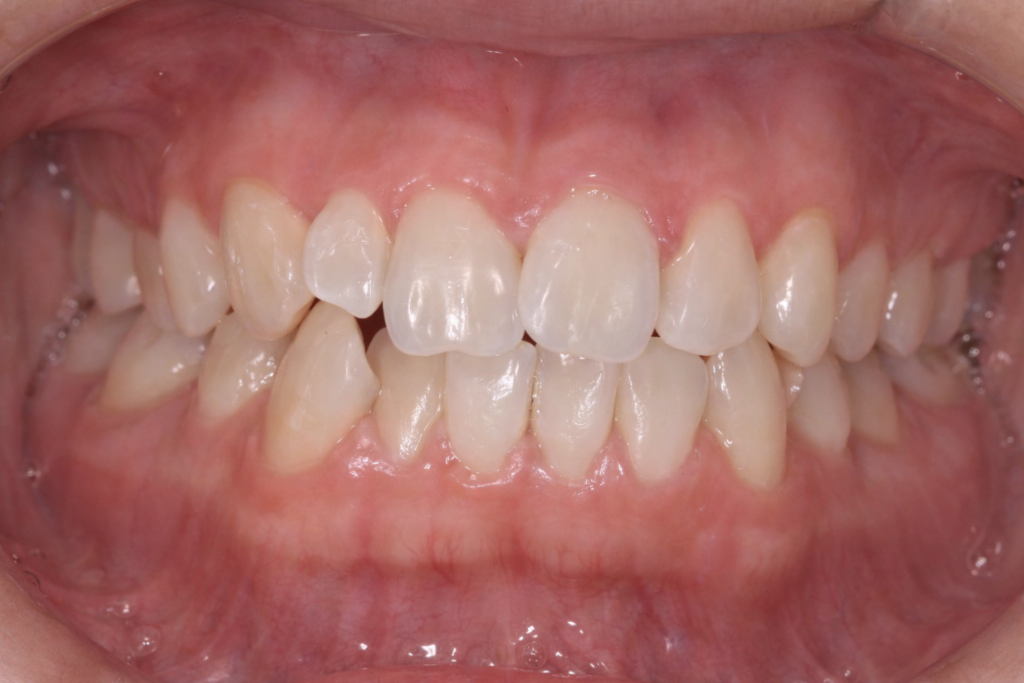

ワイヤー矯正に切り替えて改善した例

途中でワイヤー矯正に切り替えることで、

- 歯根位置を正確にコントロールできる

- 噛み合わせが安定する

- 治療が一気に進む

ケースも多くあります。